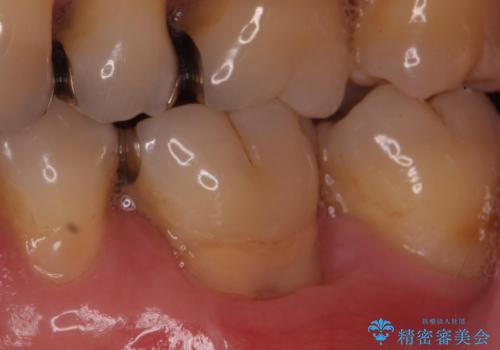

歯根の分岐部よりも根尖側の頬側面が露出している状態でしたが、露出部位を分岐部までに抑えることができました。

しみる症状も改善され、大変喜んでいただけました。

術後は歯肉が下がらないよう経過を追っていきます。